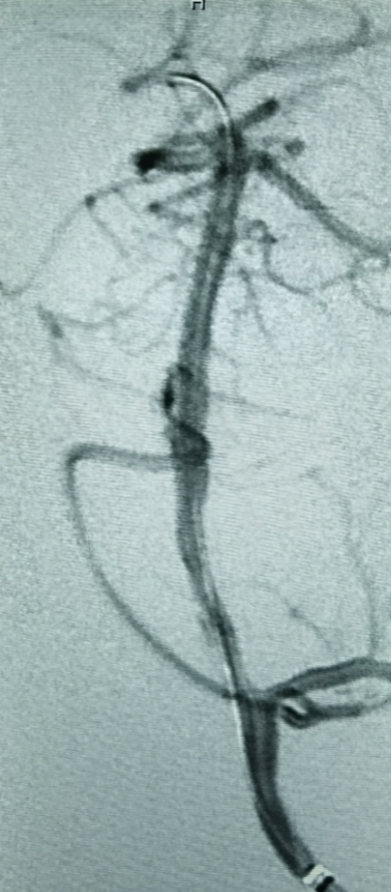

5F 115cm远端通路导管超选至左侧椎动脉V3段,选取术中工作角度造影。

、

留置300cm FATHOM微导丝,撤出微导管后造影,似乎有了一点正向血流,但压力不够,被逆向血流冲淡。